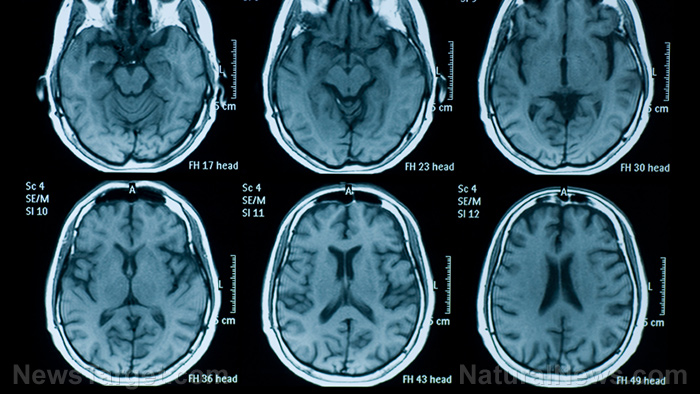

Capillary telangiectasias are small, broken or widened blood vessels on the skin that are typically harmless, but may be linked to other diseases. Capillary telangiectasias may occur anywhere within the body, but are most easily seen on the skin, mucous membranes, and whites of the eyes. They may also develop in the brain or intestines. Capillary telangiectasias may develop due to rosacea, a skin problem that causes the face to turn red, aging, a genetic problem, pregnancy, exposure to sun, varicose veins, excessive use of steroid creams, and trauma to the area. Other possible causes include excessive alcohol consumption, scleroderma, dermatomyositis, and systemic lupus erythematosus. Capillary telangiectasias are also sometimes called as “spider veins” because of their fine and web-like appearance.

Generally, capillary telangiectasia is not life-threatening. However, it can cause pain, itching, and threadlike red marks or patterns on the skin. Moreover, serious cases of this condition may cause serious complications such as hemorrhage, stroke, difficulty in speaking, loss of vision, severe unsteadiness, and hydrocephalus. If capillary telangiectasia is caused by hereditary hemorrhagic telangiectasia (HHT), a rare genetic condition, it may cause frequent nosebleeds, red or dark black blood in stools, shortness of breath, seizures, small strokes, and port-wine stain birthmark.